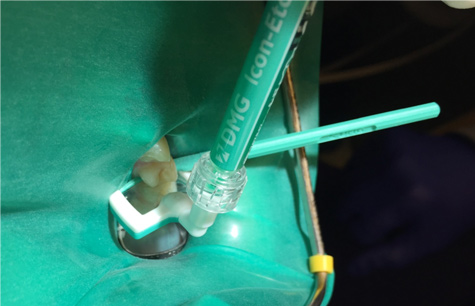

11. Insert the applicator with resin infiltration material syringe attached, and the green, perforated side facing the lesion (Figure 8).

12. Twist the syringe and flood the lesion with the infiltrant for 3 minutes. Occasionally twist the syringe slightly to introduce more infiltrant into the contact, ensuring adequate resin is available as it absorbs into the lesion body.

Fig 8. The applicator for the infiltrant is inserted.

Figure 8